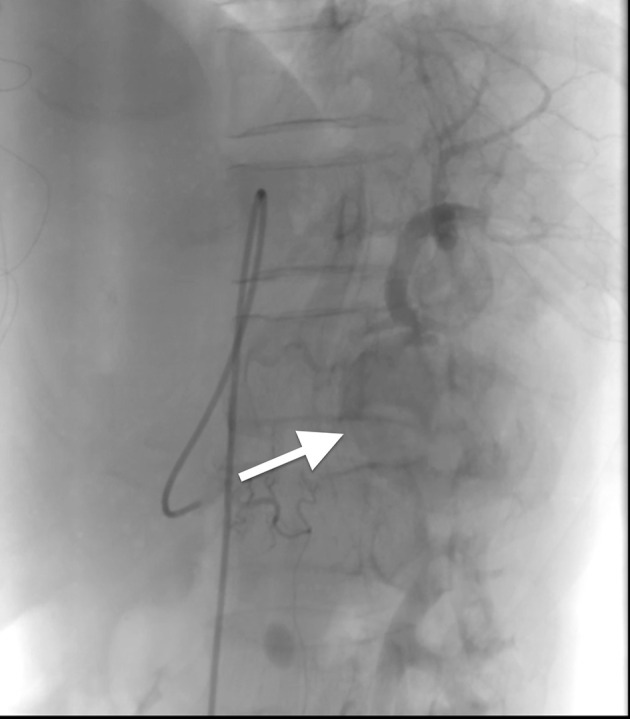

感染性心内膜炎是一种严重的感染性疾病,除了瓣膜损伤引起的心力衰竭和心律失常等心脏并发症外,还可能导致化脓症栓塞、转移性脓肿和真菌性动脉瘤等心外并发症。在此,我们报告一例罕见的由感染性心内膜炎引起的脾梗死,术后三周经CTA和DSA证实为脾动脉瘤。动脉瘤动脉栓塞后,患者最终完全康复。

Infective endocarditis is a severe infectious disease that, in addition to cardiac complications such as heart failure and arrhythmias caused by valve damage, may also lead to extracardiac complications such as septic embolization, metastatic abscesses, and mycotic aneurysms. Here, we report a rare case of splenic infarction resulting from infective endocarditis, subsequently leading to the development of a splenic artery aneurysm three weeks post-surgery confirmed both by CTA and DSA. Following arterial embolization of the aneurysm, the patient eventually recovered completely.